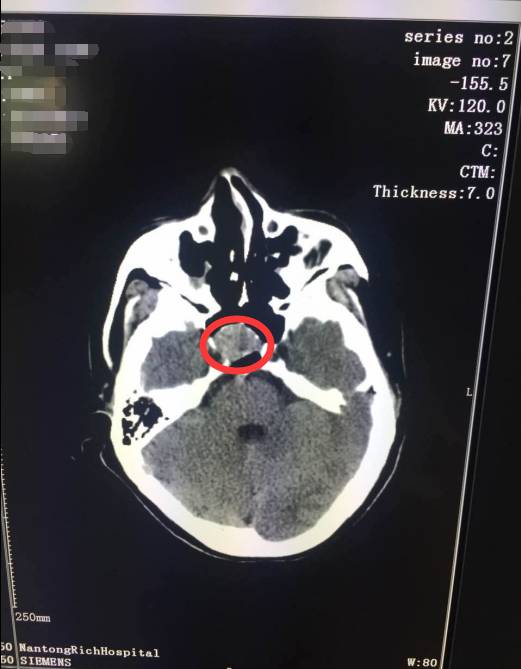

據(jù)瑞慈醫(yī)院神經(jīng)外科主治醫(yī)師錢(qián)志坤介紹,于女士的垂體瘤是大型垂體瘤,直徑超過(guò)了1厘米,形態(tài)很不規(guī)則,腫瘤偏向右側(cè),侵犯右側(cè)海綿竇,包繞右側(cè)頸內(nèi)動(dòng)脈,處理不當(dāng)?shù)脑?huà),極有可能造成頸內(nèi)動(dòng)脈、動(dòng)眼神經(jīng)等重要的血管、神經(jīng)損傷,加重病情甚至出現(xiàn)生命危險(xiǎn)。

圖為:紅圈位置即為垂體瘤